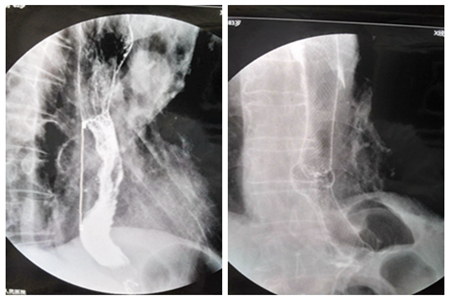

患者2,男,73岁,中下段食道癌放置支架前

(中下段食道癌支架置入术后6月,下端二次狭窄,行狭窄段再次支架置入术)、后对比图